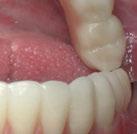

Este último aparato funcional se mantuvo en boca durante 8 meses, tras haber conseguido la mejoría esperada en cuanto al aspecto facial (figura 17) y las relaciones oclusales (figuras 18 a 22). La mordida abierta lateral producida es fácilmente solucionable en la siguiente fase de tratamiento.

(USS), como se aprecia en las figuras 23 a 25, comienza la segunda fase de tratamiento. Esta duró tan solo 12 meses debido a que gran parte de las relaciones oclusales habían mejorado durante la etapa anterior. Los resultados finales del tratamiento se observan en las figuras 26 a 30 , con la corrección de la clase molar y canina, el resalte y la sobremordida, el centrado de las líneas 1/2 y la curva de Spee. La mejoría en la macro, mini y microestética facial se aprecia en las figuras 31 a 33 , a pesar de la evidente desviación del mentón hacia